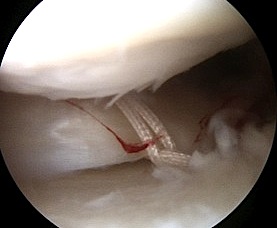

1. Red / Red longitudinal tear

- outer 3mm / meniscocapsular junction

2. Red / White longitudinal tear

- only one side of tear vascularised

Principles of Repair

1. Debride tear

- stimulate proliferative response

- remove mature scar

- with shaver / rasp

2. Trephine meniscocapsular periphery

- with spinal needle to promote vascular channels

3. Reduce mensical tear